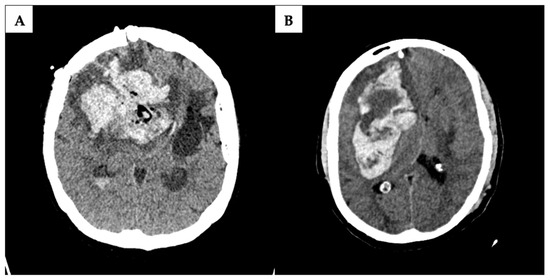

All postoperative radiologic findings were reviewed for the presence of hemorrhage. The determination of blood volume was entrusted to radiology colleagues. Hemorrhages were systematically categorized as either hemorrhage in the tumor cavity; intracerebral hemorrhage; subarachnoid hemorrhage; or subdural hemorrhage. Significant postoperative hemorrhage was exclusively recorded for patients exhibiting substantial neurologic symptoms such as impaired consciousness due to increasing intracranial pressure and requiring surgical intervention due to space-occupying hemorrhage (Figure 2). Symptomatic neurologic deficits were precisely defined as focal neurologic deficit, headache, nausea, or a change in cognitive function.

A majority of pICHs were identified as intracerebral (n = 7), with an additional prevalence observed in what is referred to as a resection cavity (n = 10), specifically post-tumor extirpation. Subdural hematoma (n = 2) and subarachnoid hemorrhage (n = 1) were comparatively less frequently identified through computed tomography. Figure 2 shows two examples where postoperative CT-imaging revealed space-occupying intracavital pICH requiring revision surgery.

Figure 2. Postoperative computed tomography scans in a patient with postoperative intracranial hemorrhage. Examples of a severe intracerebral hemorrhage in the acetylsalicylic acid (ASA) group (A) and a massive intracerebral hemorrhage in the no ASA group (B). In both cases, a second operation was required.